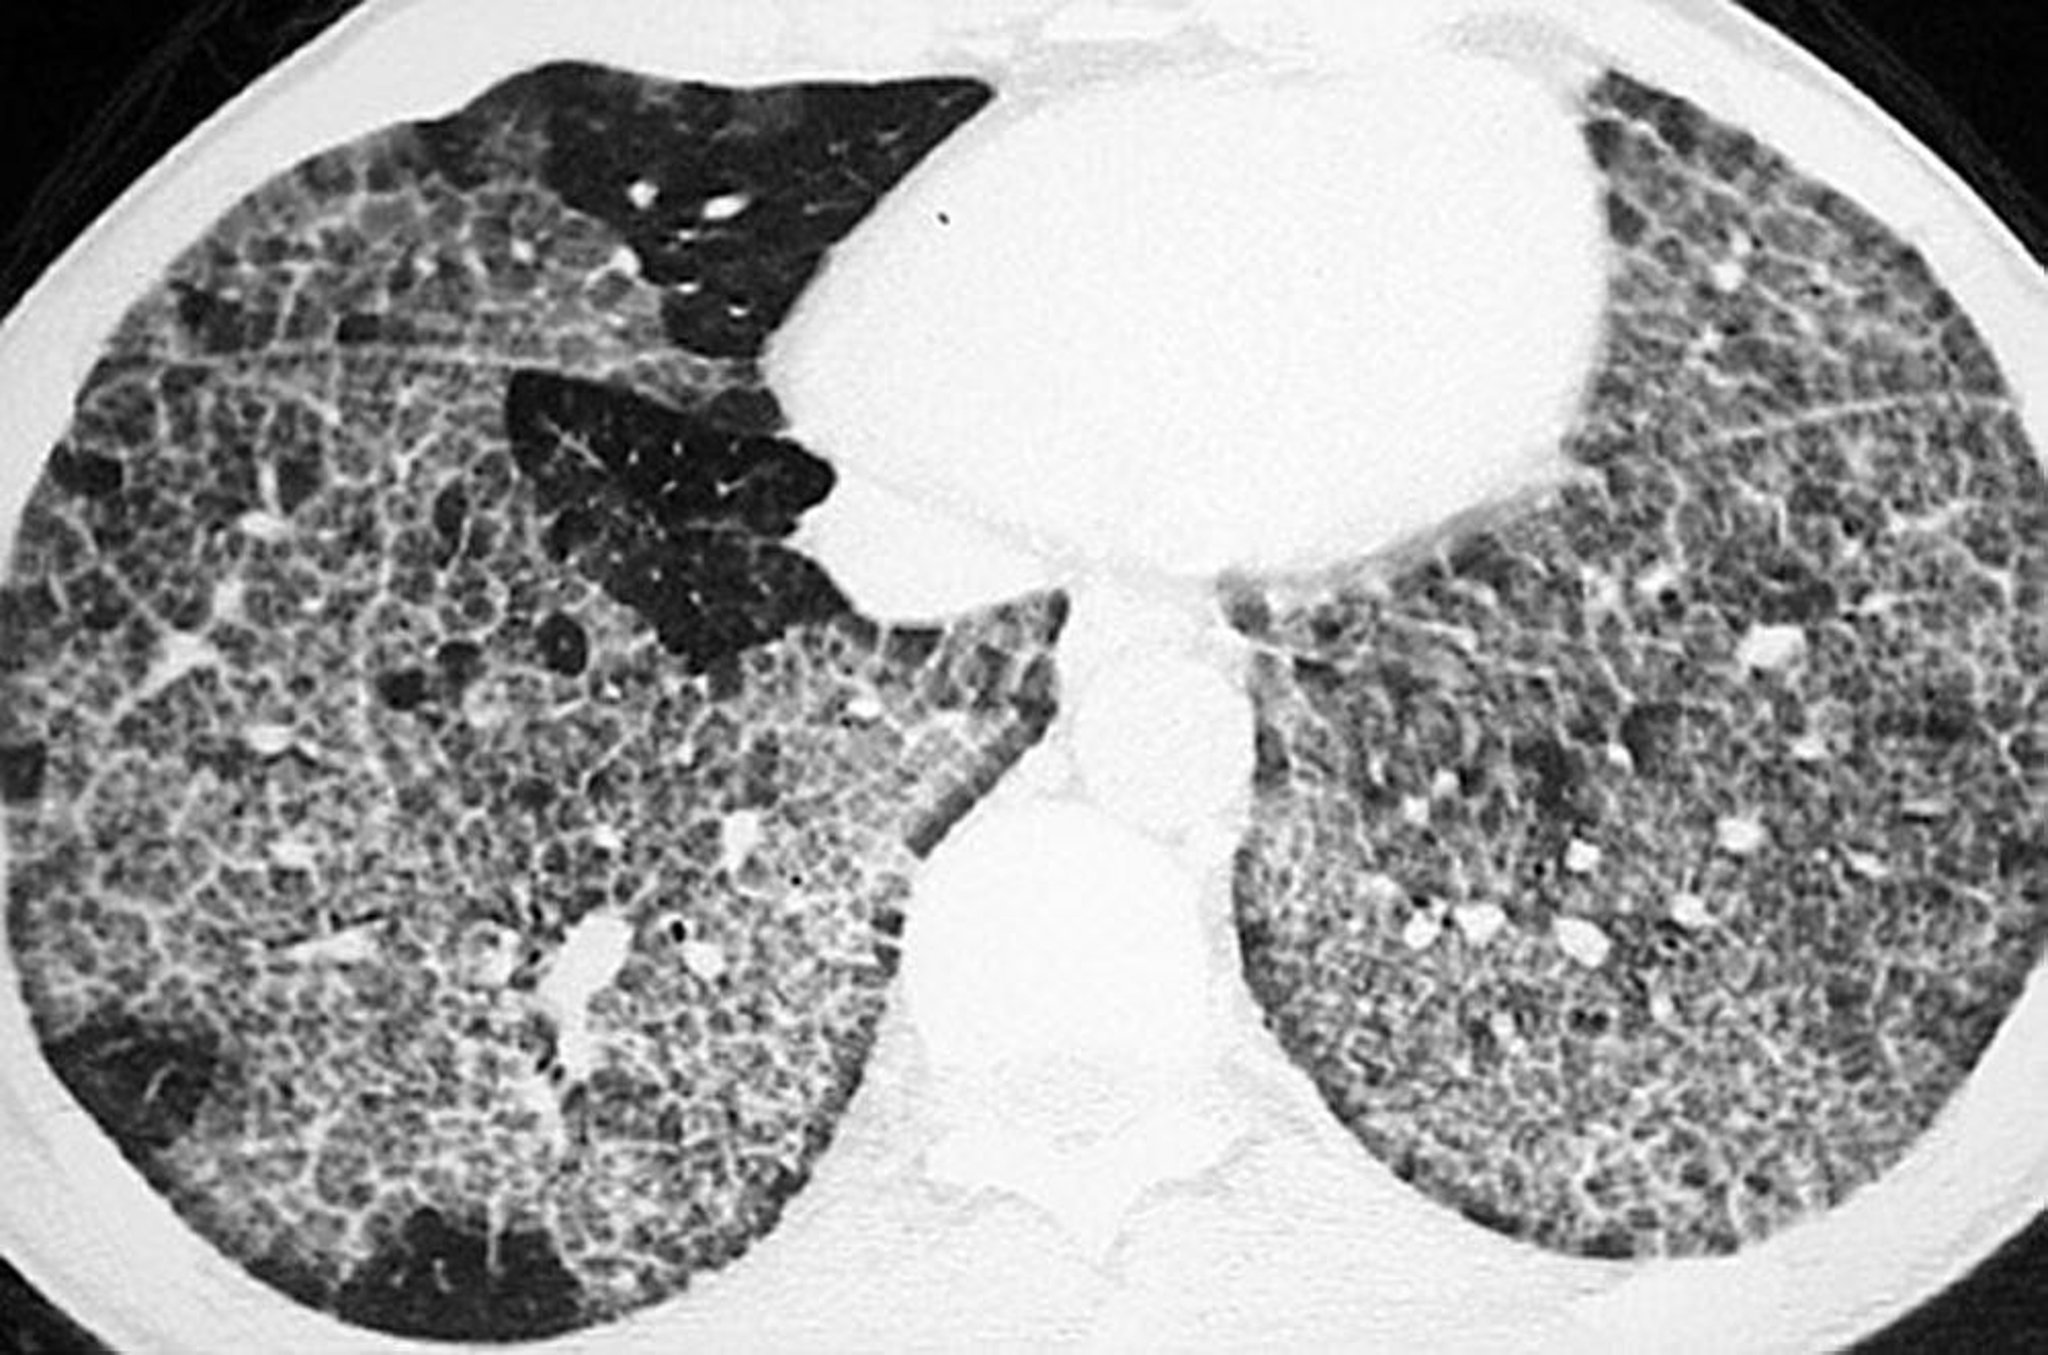

Proteinosi alveolare polmonare (TC)

La TC ad alta risoluzione mostra opacità a vetro smerigliato e ispessimento delle strutture intralobulari e setti con aspetto poligonale ("crazy-paving").

Image courtesy of Talmadge E. King, MD.